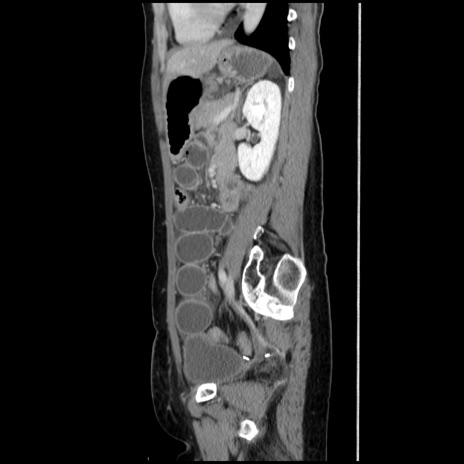

症例32(矢状断像)

【症例】40歳代 女性

【主訴】上腹部痛、嘔気・嘔吐

【現病歴】約9時間前頃から急に上腹部痛、嘔気、嘔吐が出現。改善しないため救急要請。

【既往歴】子宮頚癌(広汎子宮全摘術、放射線療法)、腸閉塞

【身体所見】腹部:平坦、軟、腸雑音亢進、上腹部を中心に腹部全体に圧痛あり。

【データ】WBC 8400、CRP 0.03